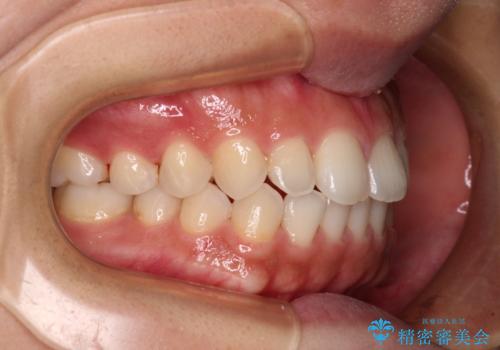

インビザラインを用いた上顎の部分矯正

- 上顎前歯の叢生を気にして来院された患者様です。

下顎前歯や上下奥歯の咬み合わせには殆ど問題がないため、上顎前歯のみを矯正する治療を提案しました。

ワイヤー装置でもインビザラインでも可能でしたが、前歯のみをきれいに排列するのであればインビザラインの方が仕上がりが良いので、インビザライン・ライトにて治療を行うこととしました。